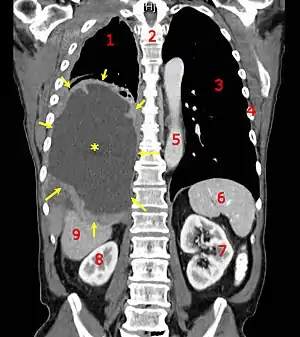

| A coronal CT scan showing a malignant mesothelioma Legend: → tumor ←, ✱ central pleural effusion, 1 & 3 lungs, 2 spine, 4 ribs, 5 aorta, 6 spleen, 7 & 8 kidneys, 9 liver. | |